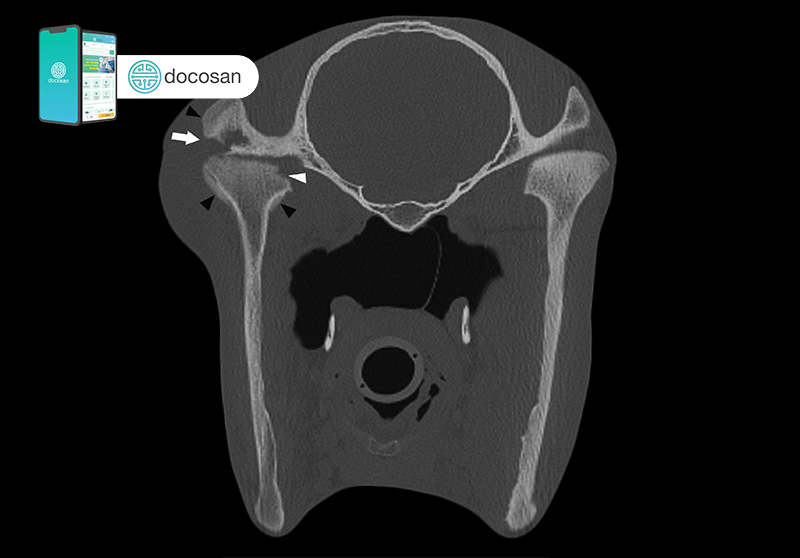

Khi có các dấu hiệu được nêu trên, bạn nên đến phòng khám răng hàm mặt để được chẩn đoán và điều trị kịp thời. Bác sĩ sẽ quan sát, nghe và sờ nắn vùng khớp thái dương hàm của bạn trong các vận động há mở, tới lui và đưa hàm sang bên. Khi phát hiện có vấn đề bất thường, bạn sẽ được cho chụp phim X-quang sọ nghiêng, Conebeam CT, MRI… tùy theo chỉ định của bác sĩ.